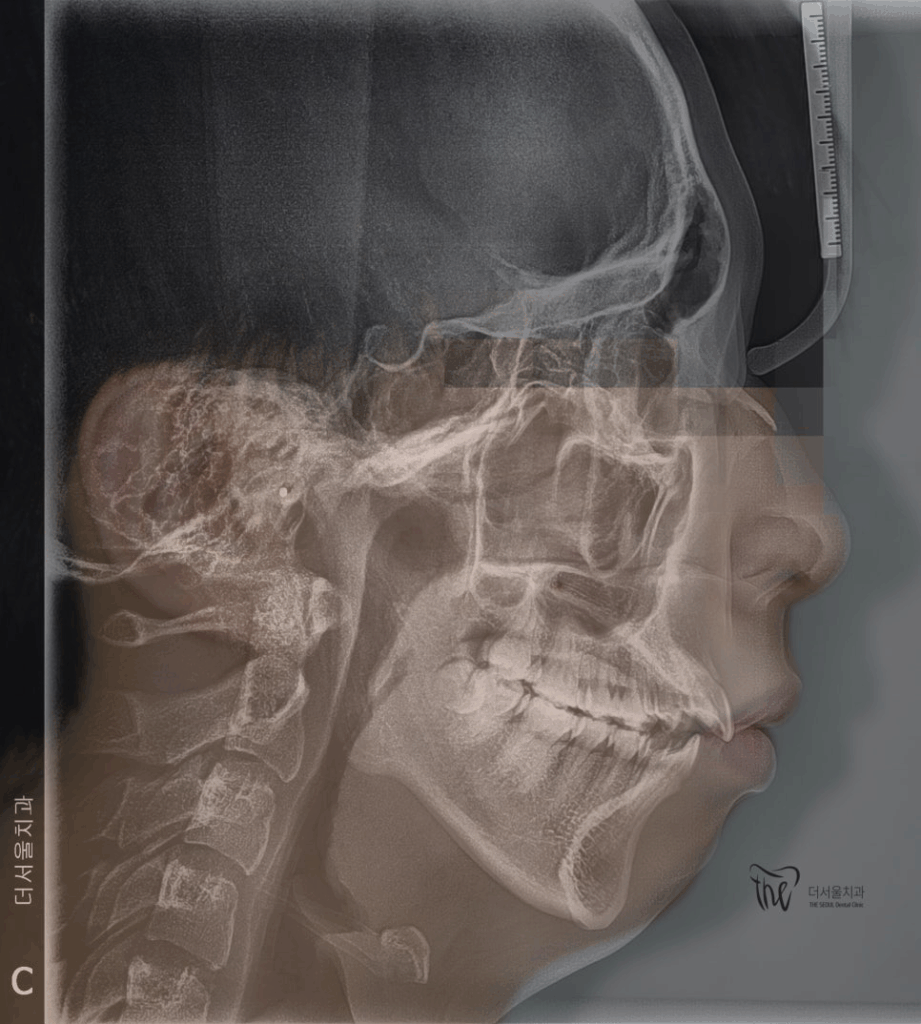

측면 두부방사선 사진 및 안모의 측면사진의

중첩 된 결과입니다.

사진을 보면, 턱이 거의 없는 무턱 증세를 띄고

있는 것이 한 눈에 보여집니다.